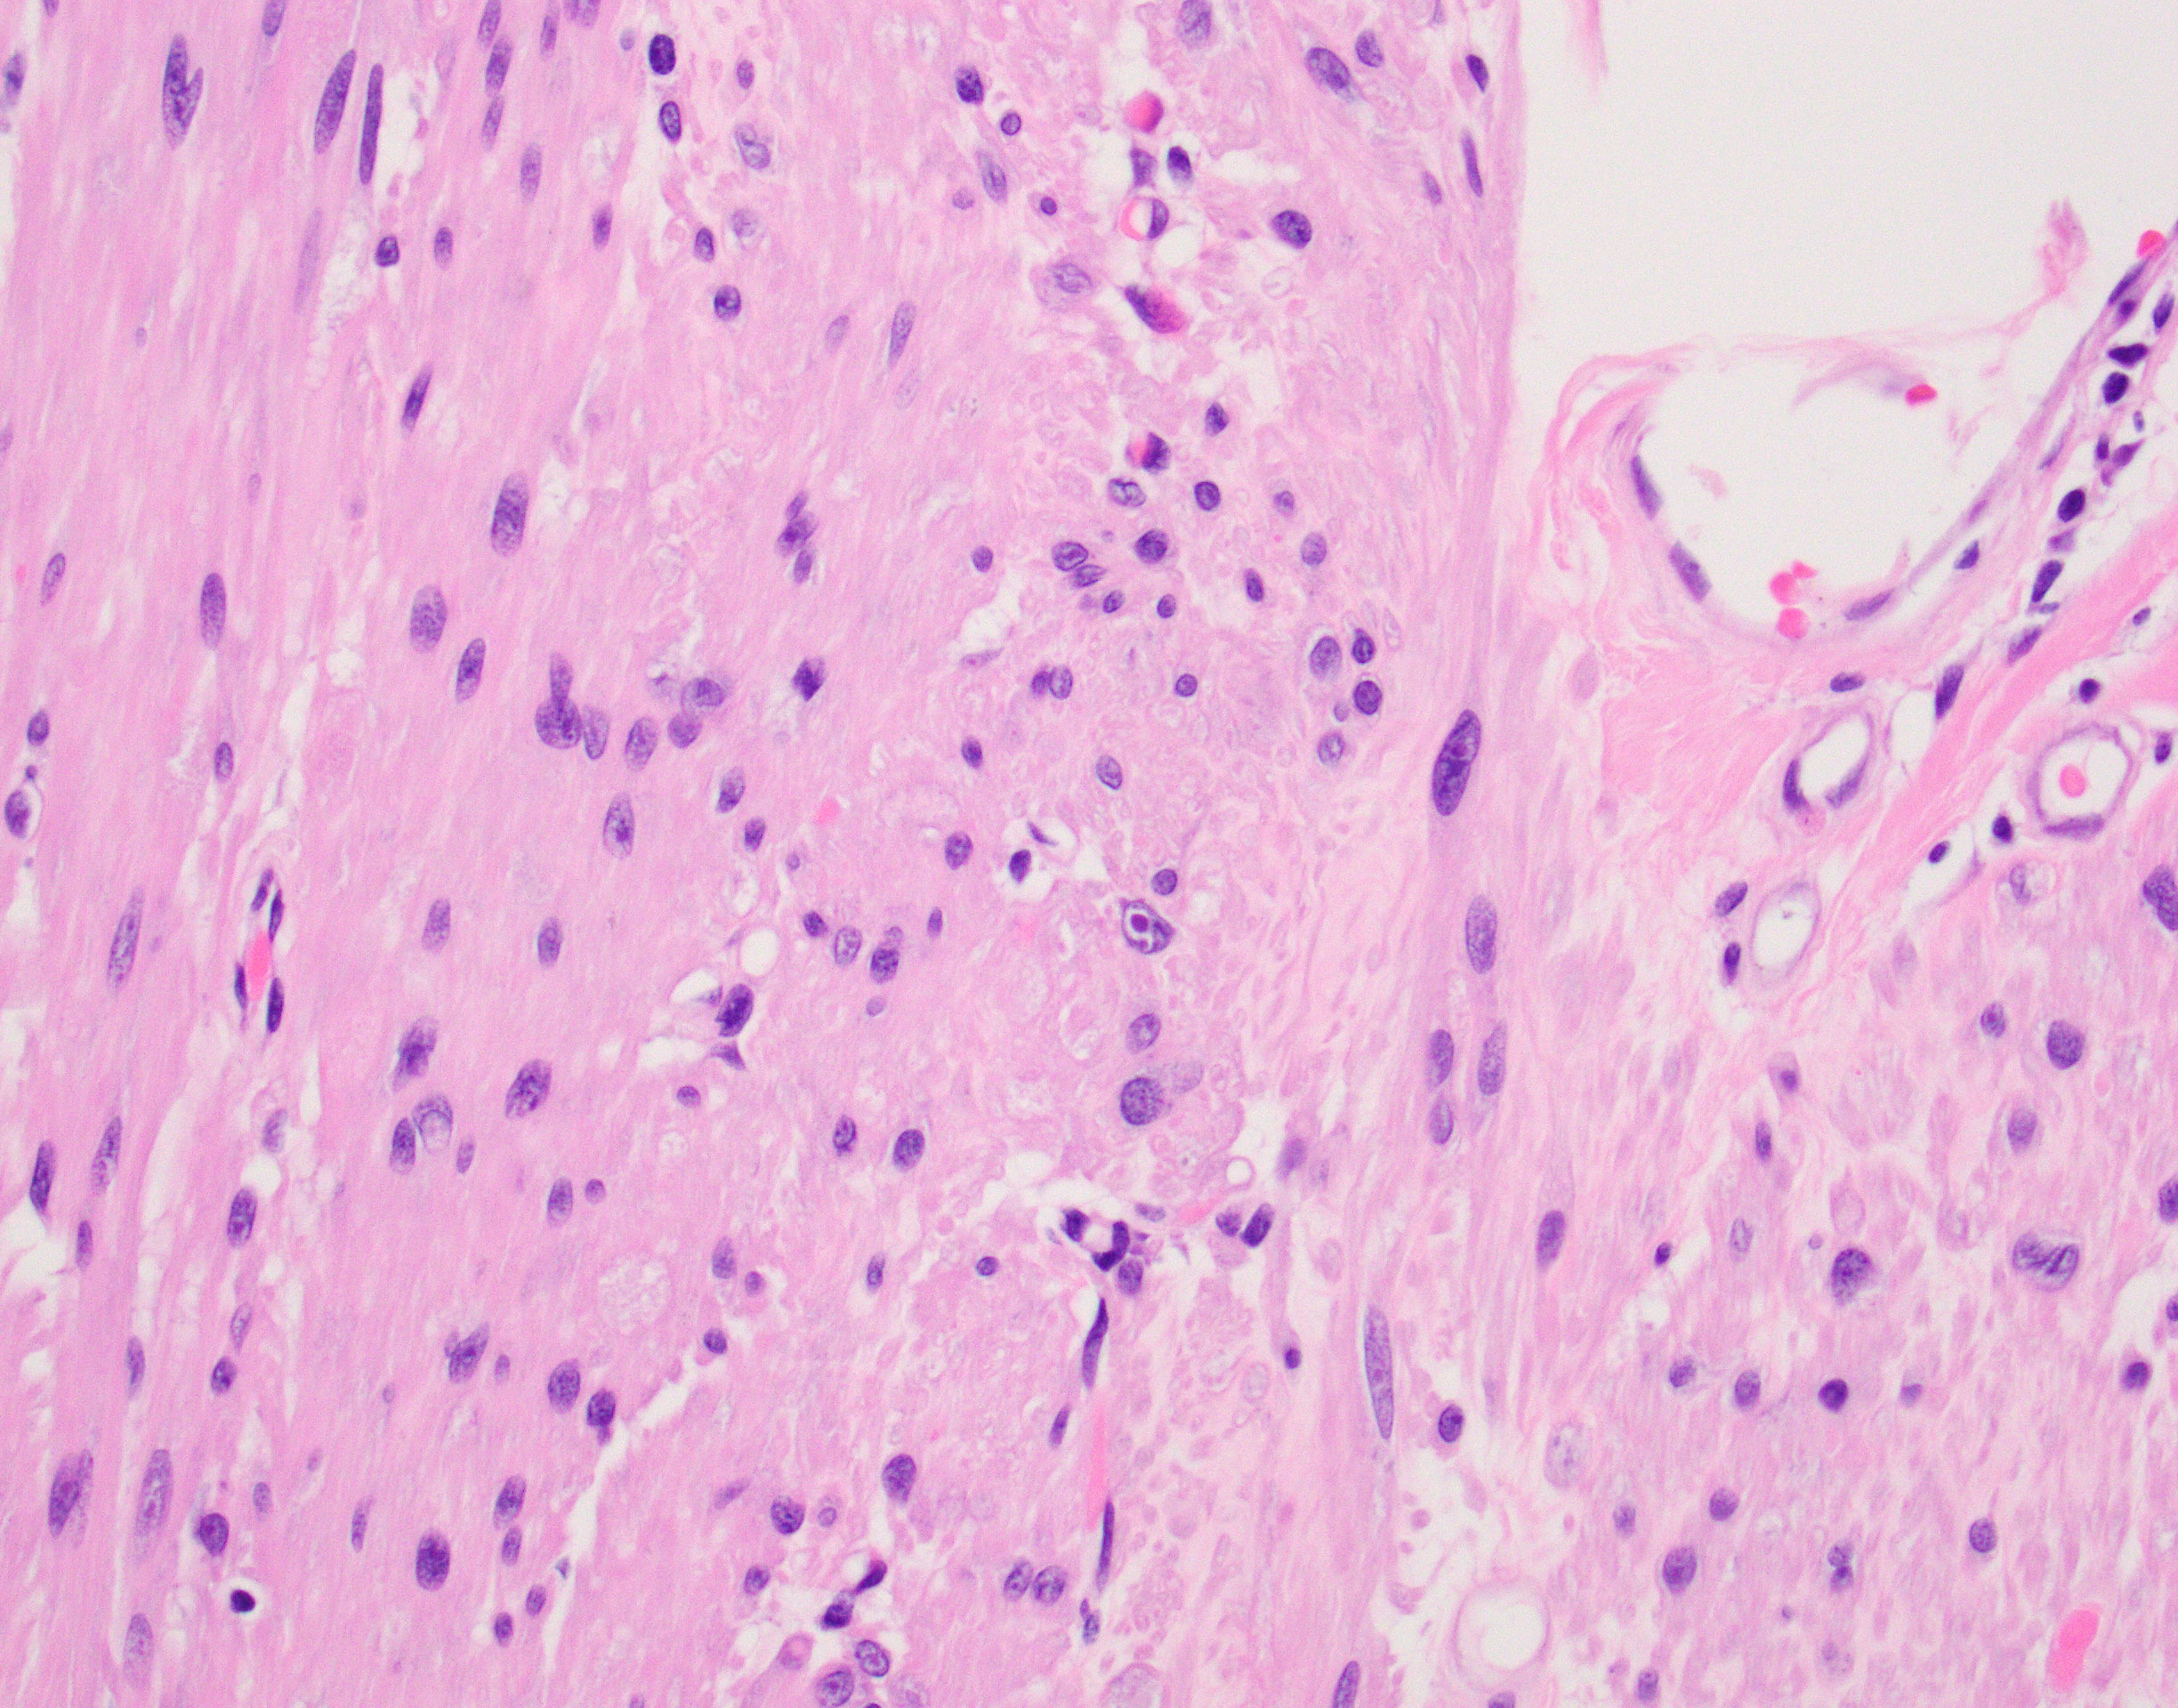

The patient is showing well-circumscribed (Fig 1) leiomyomatous lesions with features of the Hereditary Leiomyomatosis and Renal Cell Cancer (HLRCC) Syndrome (OMIM 150800, AKA Reed’s syndrome) which is produced due to germline mutations of the gene coding for the mitochondrial enzyme Fumarate Hydratase (FH, 1q43). This syndrome is characterized by multiple cutaneous, and in women uterine, leiomyomas exhibiting some distinctive features seen in this particular lesion; mainly cytoplasmic eosinophilic globules (Figure 2), nuclei with powdery chromatin exhibiting prominent nucleoli (Figure 3). Uterine examples tend to show similar albeit more pronounced nuclear features in addition to Hemangiopericytoma-like (HPC-like) vasculature, nuclear periodicity among other unique characteristics. Likewise, renal cell carcinomas arising in the context of HLRCC have their own set of distinct features including similar powdery chromatin and large nuclei with viral-like macronucleoli. These renal tumors were historically classified as type II papillary renal cell carcinomas (RCCs) or unclassifiable RCCs. The absence of the normal enzyme can be demonstrated by immunohistochemistry for Fumarate Hydratase (FH), which will show loss of staining in the lesional cells like in our case (Fig 4). In addition, one could performed immunohistochemistry for the abnormal product of the mutated FH gene (2-Succinocysteine, 2SC) a test that is not widely available.